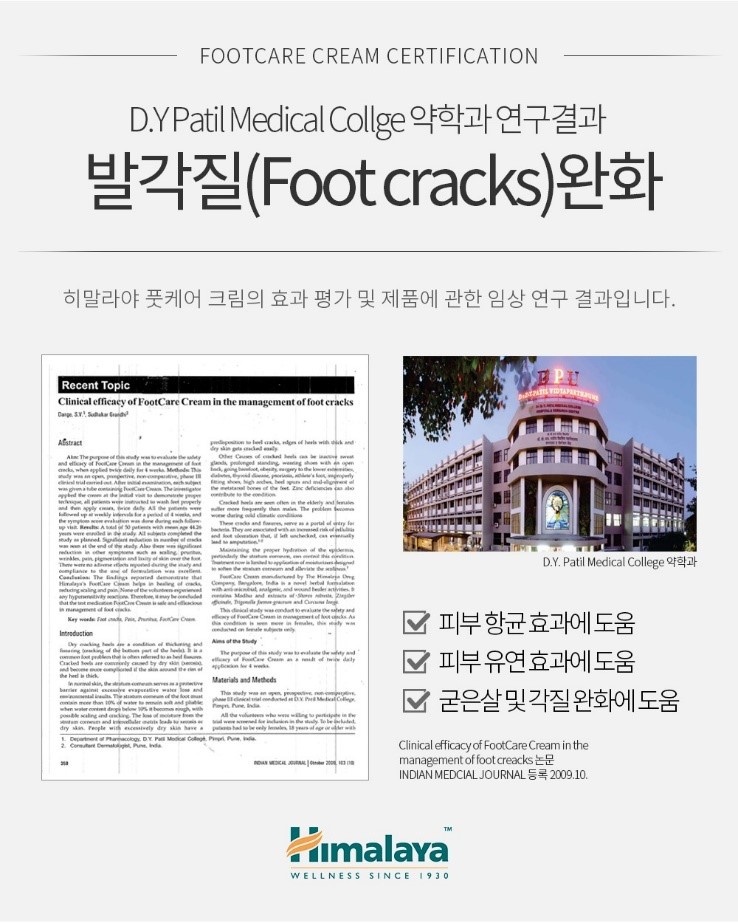

90년 이상의 역사와 전통의 히말라야 브랜드로

전 세계 의사, 약사, 자연과학자 등

400여 명의 연구진이 제품 제작에 참여하고

신제품 출시 전 다양하고 체계적인 10년간의 연구 개발의 과정을 거치고

1,112개의 임상실험 의학논문은

세계의 다양한 저널에 등록되어 그 과학성을 입증하는 브랜드